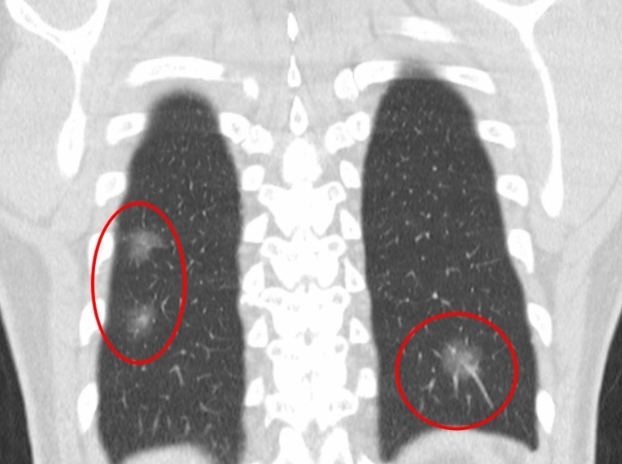

흉부 엑스레이 결절음영

결절음영이란 말은 엑스레이에서 ‘혹처럼 보이는 부분’을 뜻해요. 작게 하얗게 보이는 점, 혹은 둥근 모양의 그림자가 결절음영입니다. 이게 보이면 대부분은 오래된 염증, 흉터, 석회화(염증이 낫고 남은 흔적)일 때가 많아요.

하지만 간혹 크기가 크거나 모양이 울퉁불퉁한 경우엔 폐암 같은 질환을 의심하기도 합니다. 그래서 보통은 “추적 관찰”을 권해요. 6개월 또는 1년 뒤 다시 찍어서 변화가 없는지 보는 거죠. 제 지인 중 한 분도 건강검진에서 결절음영이 나와서 놀랐지만, 재검 때는 흔적만 남고 없어졌어요. 그때 이후로는 주기적으로 검사받는 걸 잊지 않으신다고 하더라구요.

흉부 엑스레이 폐암

폐암은 초기에 특별한 증상이 거의 없어서 조기 발견이 어렵습니다. 흉부 엑스레이는 폐암을 찾아내는 첫 번째 단계로 사용돼요. 작은 혹이나 결절이 보이면 추가로 저선량 CT(방사선량이 적은 컴퓨터 단층촬영)를 진행하게 되죠.

하지만 엑스레이만으로 모든 폐암을 잡아내긴 어려워요. 종양이 아주 작거나 혈관 뒤쪽에 숨어 있으면 안 보일 수도 있습니다. 그래서 흡연력이 있거나 가족력이 있는 분들은 1년에 한 번 정도 저선량 CT를 병행하는 게 좋아요. 저희 아버지도 금연 후 매년 CT를 찍고 계신데, “한 번 찍으면 마음이 편하다” 하시더라고요. 그 말이 참 와닿았어요. 예방이 곧 안심이니까요.

Q3. 흉부 엑스레이에서 결절이 보인다고 하는데, 꼭 암인가요?

A. 대부분의 결절은 암이 아닙니다. 예전 감염의 흔적이나 석회화된 조직이 남은 경우가 훨씬 많아요. 하지만 결절의 크기나 모양, 가장자리 윤곽이 불규칙하다면 악성 가능성도 있으므로 정기적인 추적검사를 권합니다. 요즘은 저선량 CT로 더 정확하게 관찰할 수 있습니다.